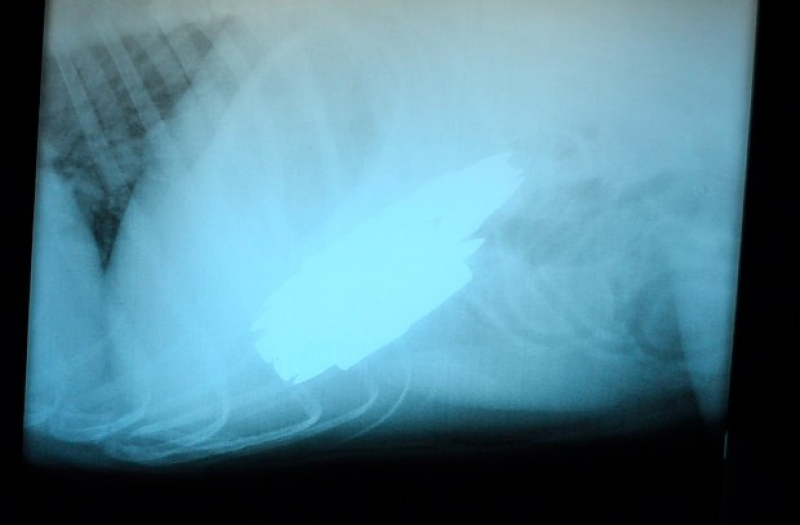

O cão chamado Benno, de quatro anos, precisou passar por uma cirurgia de emergência em um hospital nos EUA, após devorar nove cartuchos calibre .308.

O cachorro da raça pastor-belga malinois deve se recuperar totalmente da cirurgia de duas horas. O procedimento para retirada das munições foi realizado pela veterinária Sarah Sexton.